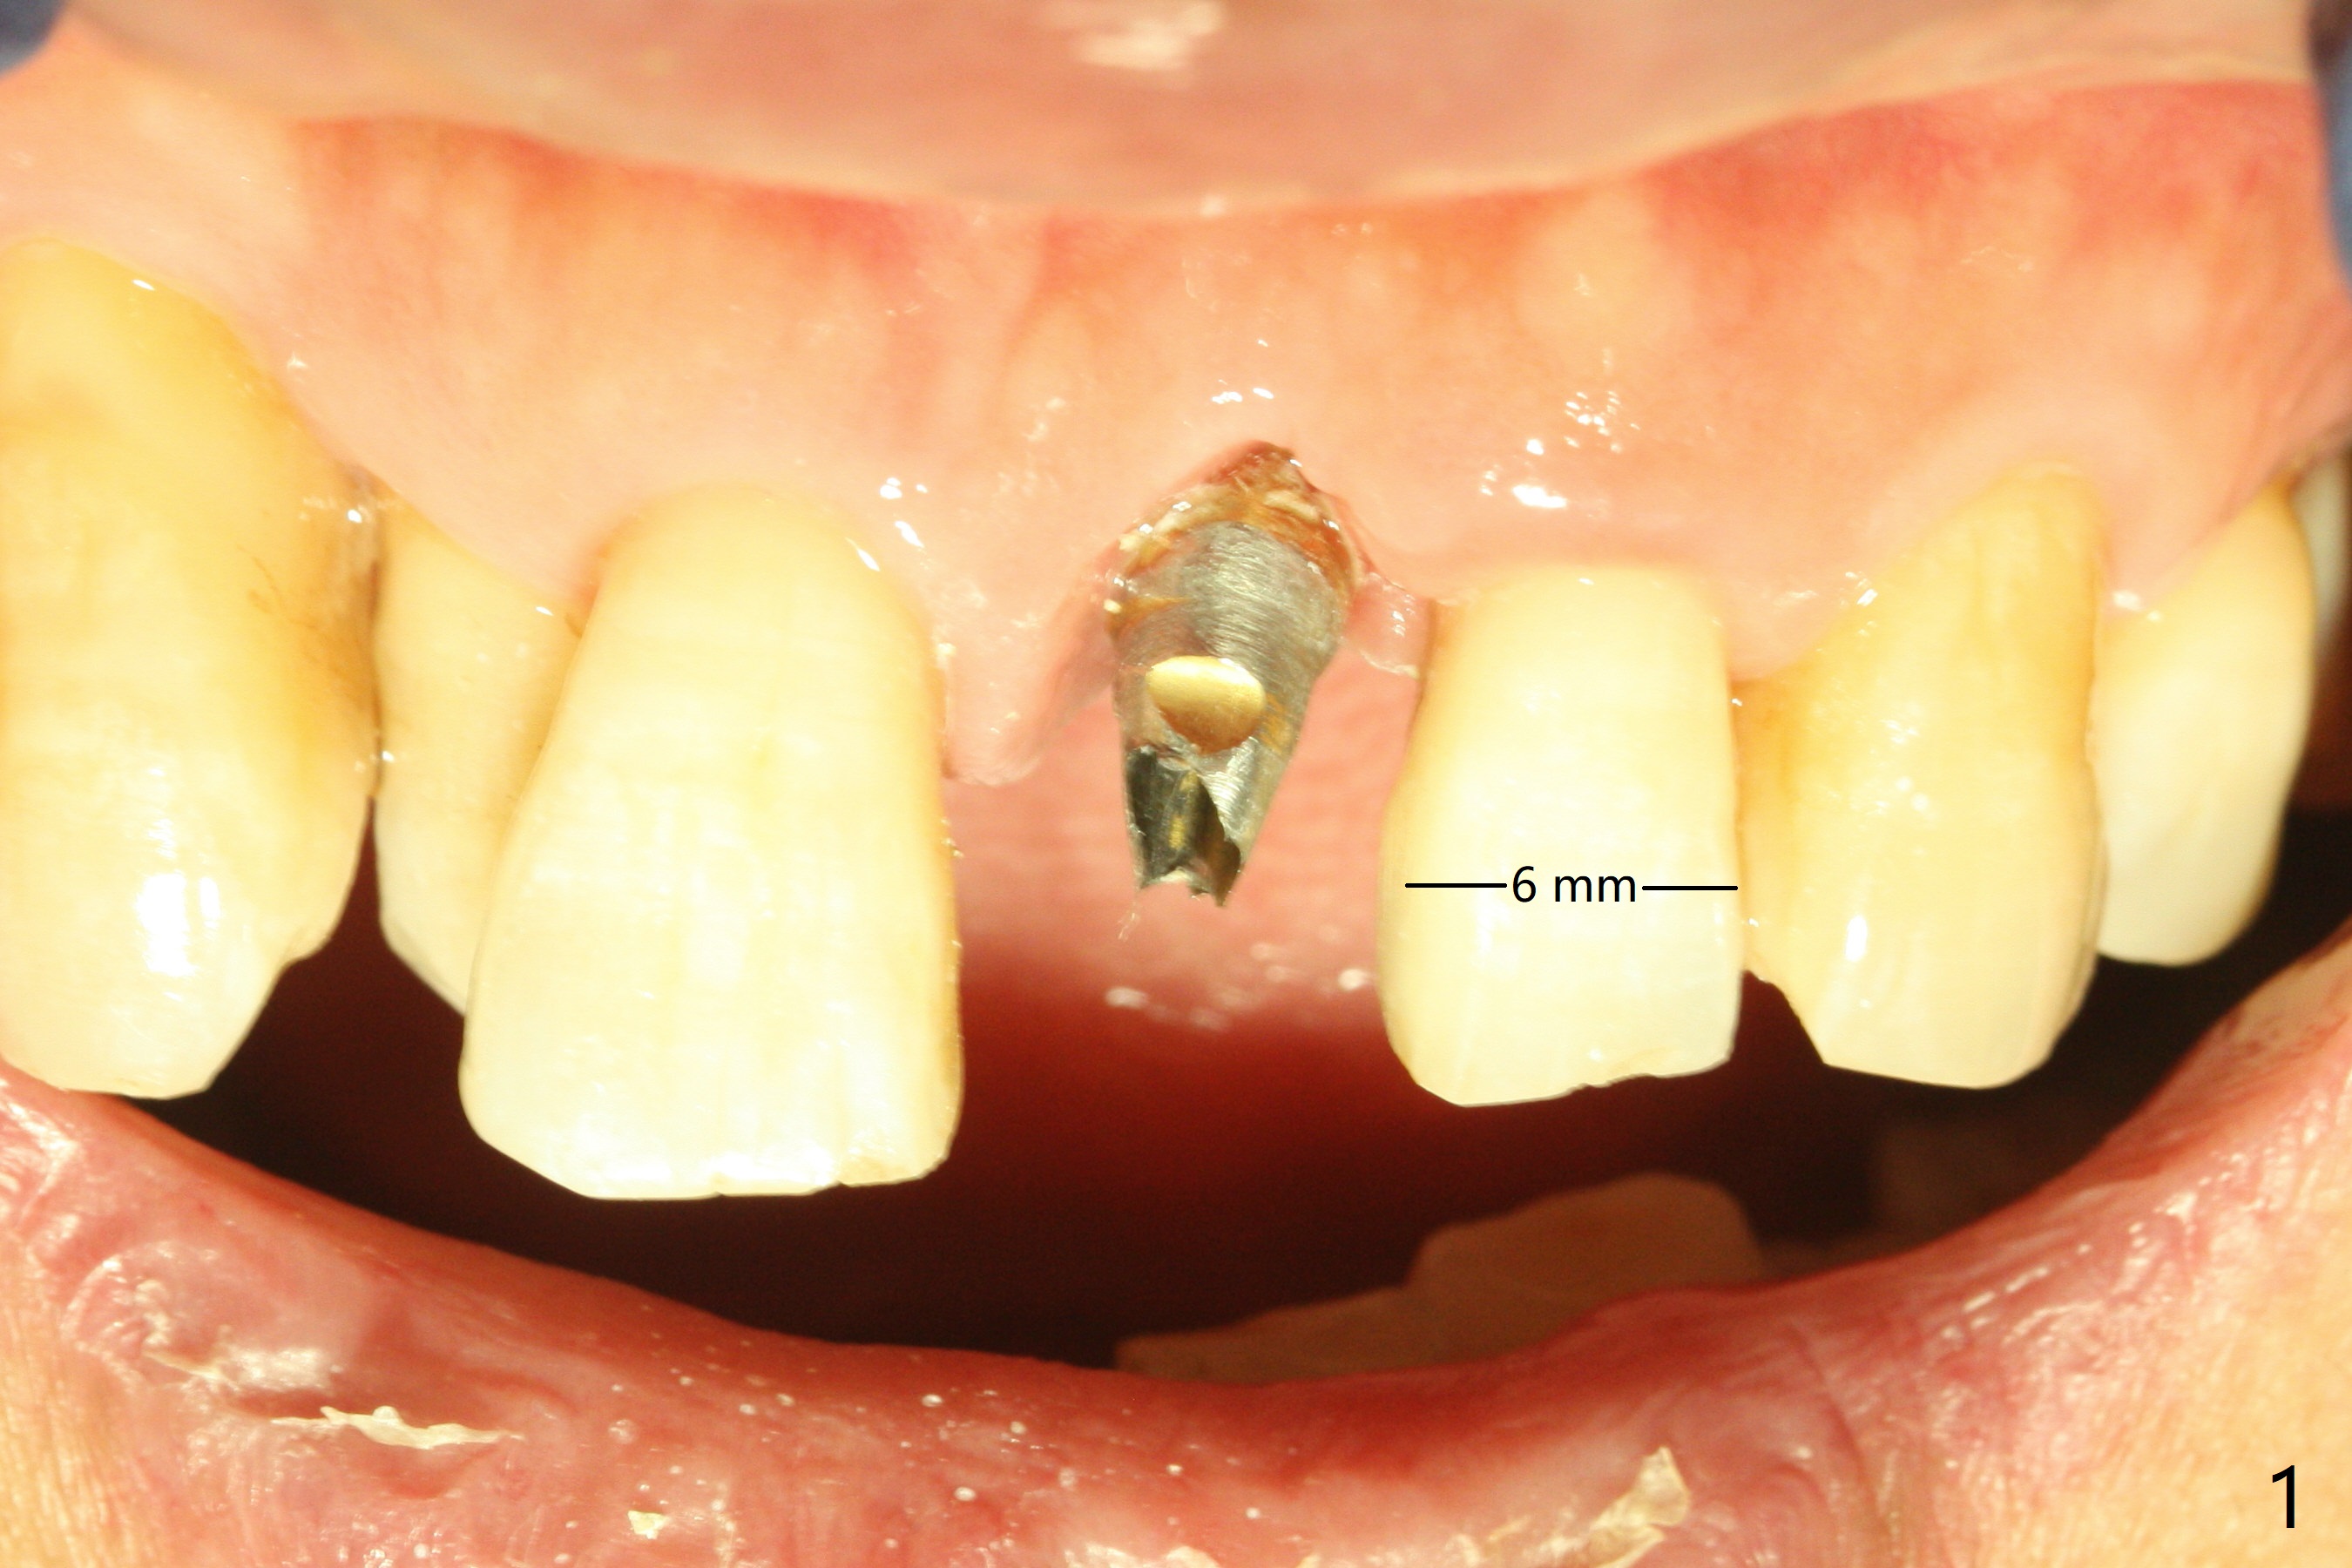

Limited Ortho with Proximal

Reduction

Nearly 7 months postop, the immediate provisional at UL1 is removed; with the mesial reduction of UL2 from 7 to 6 mm (Fig.1), an angled abutment is to be changed (4.5x15 degree, 2 mm cuff). A new provisional (Fig.2,3) co-incides with the facial midline. Brackets will be placed between UR4 to UL3 except UL2 (symptomatic once with chronic periodontitis) with initial proximal reduction between UR1-4 in preparation to correct cross bite of UR2. Twelve days later, the patient returns for UR5-UL3 bracketing after UR1-4 initial proximal reduction with 14 niti wire (Fig.4-6). UR1 moves mesial 20 days post open coil spring (Fig.7 arrow), while UL1 debracketes after permanent re-cementation of the temporary crown last visit (*, no re-bracketing, since it appears not essential). Before placement of 20 ss wire, diastemata are created by proximal reduction (Fig.8 *). In fact UR1 moves mesial, while UR3 does not move distal with the open coil. With placement of UR6 (implant) molar band, UR3 is distalized effectively. With sling shot, UR2 is almost labialized in one appointment (Fig.9). After consolidation of the diastemata between UR1-6 with power chains following UR2 cross bite correction (Fig.10), the restoration space for UL1 seems to be too large (Fig.11). Next visit, check the midlines, take 1-2 PAs for #7-9 and determine whether a straight abutment should be changed back and whether composite should be placed UR1 mesial to reduce the space. One week later, composite is added to the mesial surface of the tooth #8 to increase its width, while the provisional at #9 is relined to improve the interdental papilla (Fig.12). Minimal bone loss at UR2 is observed 8 months post banding (Fig.13), while the socket at UL1 seems to have healed except the most coronal 1 year 3 months postop (Fig.14 *). The margin of the abutment should be uneven, more coronal proximal than buccopalatal (Fig.15). The final crown has an open margin, partially due to less ideal trajectory (Fig.16 (black line: ideal trajectory, nearly 1 year 4 months postop)). Guided surgery could solve the problem. Sticky bone may restore the buccal plate defect. Die shows that the implant is palatally placed (Fig.17). CT will be taken to determine whether the implant perforates the palatal plate.